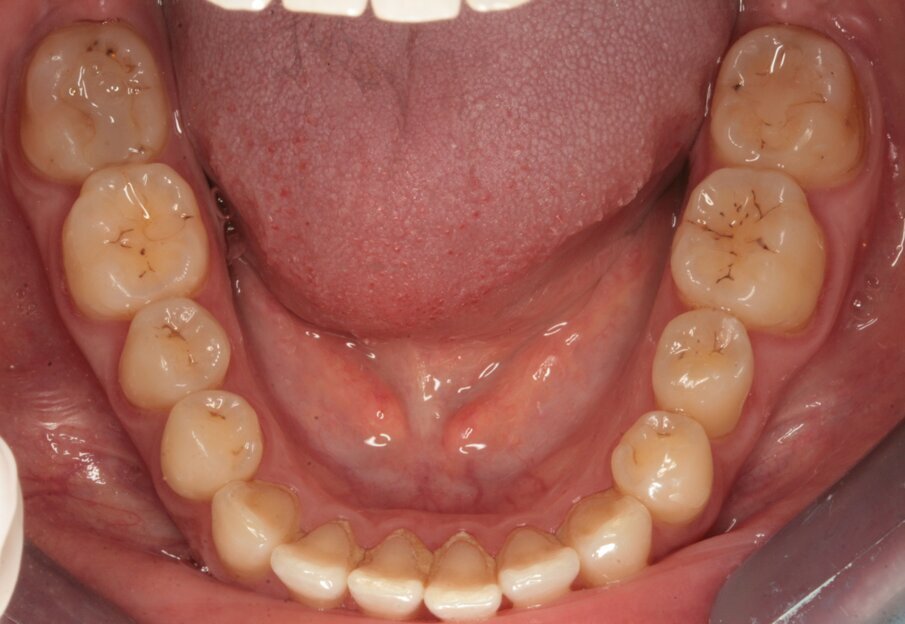

Fig. 2_Visione occlusale dell’arcata inferiore.

La paziente, FF di anni 38, è giunta alla mia osservazione per la cura delle lesioni cariose presenti. All’esame obiettivo non erano evidenti lesioni cariose di notevole entità (Figg. 1, 2): solo attraverso le bite-wing (Figg. 3, 4), mezzo indispensabile per la diagnosi odontoiatrica in conservativa, si evince la presenza di numerose lesioni cariose coinvolgenti il tessuto dentinale. La paziente richiedeva il raggiungimento di un risultato estetico ottimale, ovvero la mimetizzazione del materiale composito con il tessuto smalteo; oltre a questa esigenza si doveva unire quella di effettuare una riabilitazione funzionale ovvero, trattandosi del settore posteriore, che sopportasse il carico masticatorio garantendo la minima usura possibile nel tempo. Alla paziente è stato proposto un piano di trattamento che prevedeva la cura diretta delle lesioni cariose suddivise per quadranti e la riabilitazione indiretta dell’elemento 47 in modo da permettere la migliore precisione marginale garantendo un ottimo follow-up a lungo termine. Si è proceduto con la riabilitazione mediante il composito di recente introduzione Enamel Plus HRi Bio Function (Micerium, Avegno, Genova). Bio Function è disponibile in 3 smalti: BF1 basso valore - BF2 medio valore - BF3 alto valore e in 9 dentine: BD0 - BD0,5 (per restauri di denti particolarmente bianchi o sbiancati) BD1 (A1 Scala Vita) - BD2 (A2 Scala Vita) - BD3 (A3 Scala Vita) - BD3,5 (A3,5 Scala Vita) - BD4 (A4 Scala Vita) BD5 - BD6.